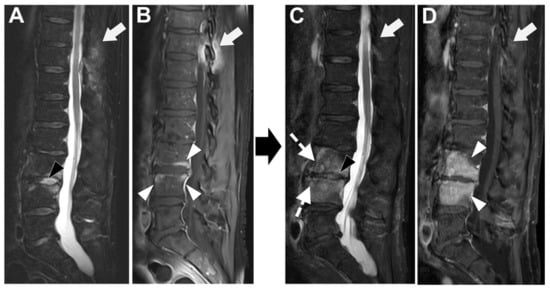

Figure 6. Tubercular spondylodiscitis. A 24-year-old man of Sudanese origin presented with thoracic and lumbar pain evolving for several months. An MRI was performed with (A) T2-weighted imaging (WI) and (B) contrast-enhanced (CE) T1-WI, as well as a CT-scan in bone kernel (C) and abdominal kernel after contrast medium injection (D,E). It demonstrates preserved disk but extensive sub ligamentous collections spreading along the anterior side of the thoracic and lumbar vertebral bodies (white arrowhead), but also along the posterior vertebral collateral ligament (white arrows) with large anterior and posterior erosions (black arrows). Please note the extensive collections spreading in the presacral space and along bilateral iliopsoas muscles without surrounding inflammation (white dashed arrows).

In Figure 6 an exemplificative case of TbS is presented.